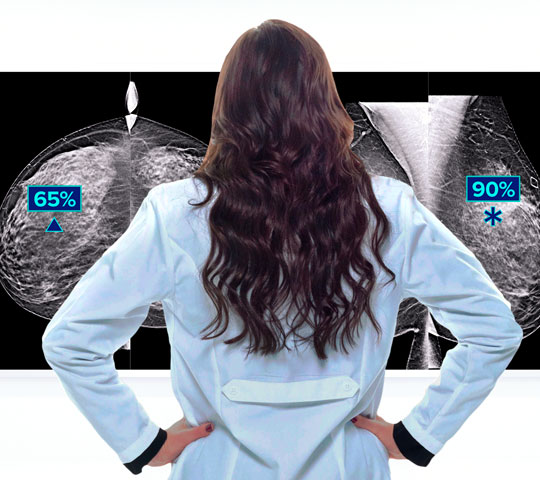

Reduce Recalls

Detects up to 65% more invasive breast cancer, and reduces recalls by up to 40%, compared to 2D alone.2-4,*

Superior Accuracy

Superior accuracy for women with dense breasts compared to 2D alone.6